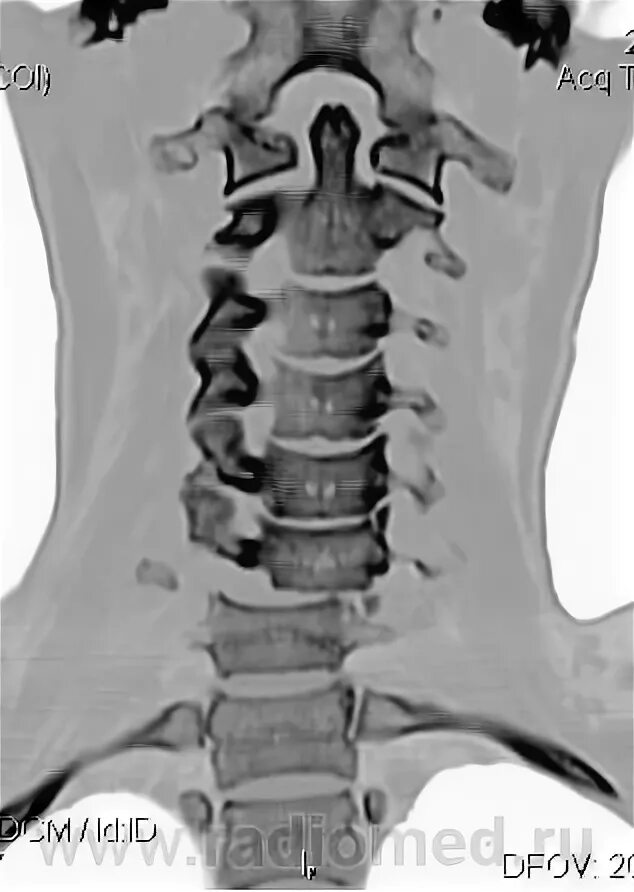

Перелом отростка l2